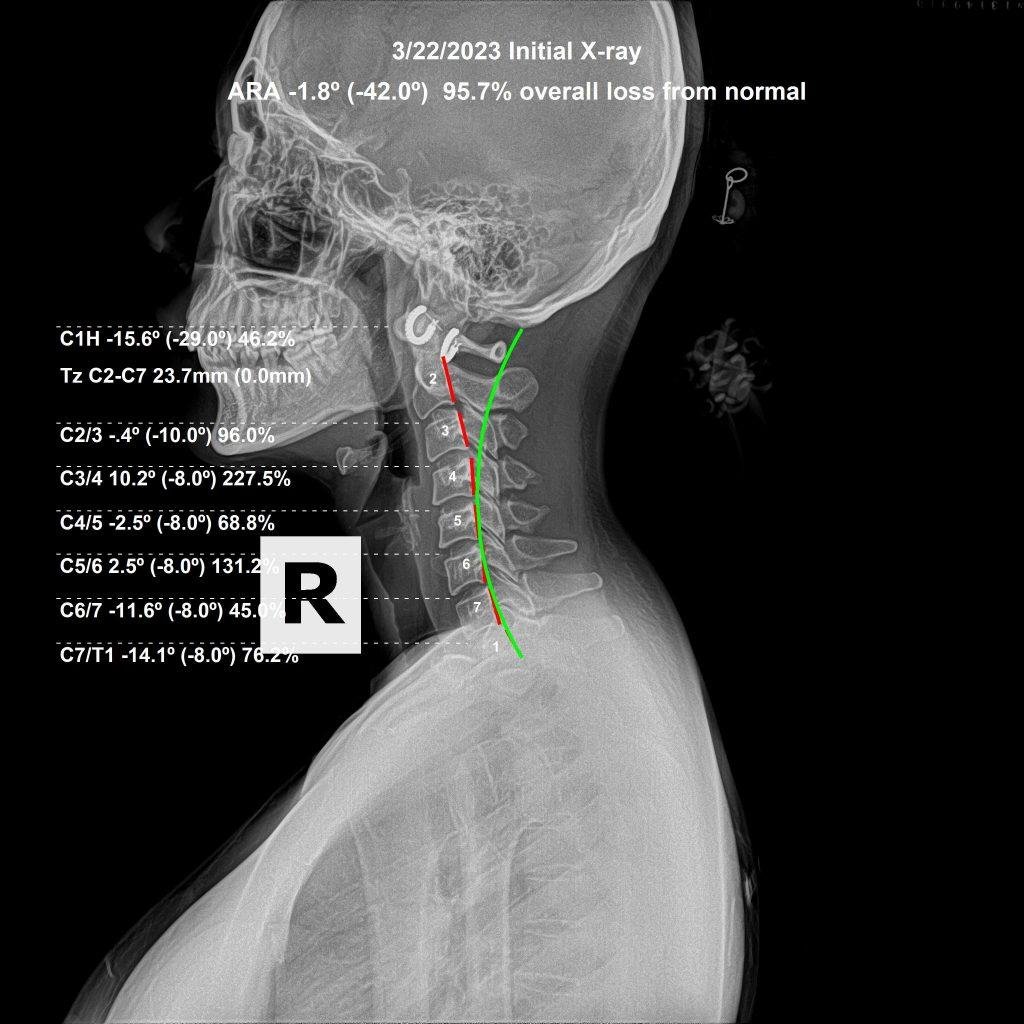

Lateral cervical X-ray showing cervical curve analysis — Rochet Family Chiropractic Royal Palm Beach FL

Lateral cervical X-ray. The curve of the neck, vertebral positioning, and disc spaces are all evaluated for subluxation. Dr. Rochet, Royal Palm Beach FL.

Before & After Structural Analysis

Subluxation correction is not a single event. It is a process of progressive structural change over time, documented through follow-up X-rays taken after a period of care. The before-and-after films below are representative of what correction actually produces — measurable, visible change in spinal position and cervical curve.

Before cervical X-ray — subluxation present, reduced cervical curve

Before Correction

What you are looking at is a change in the structural position of the cervical vertebrae — the curve deepening, the head position normalizing, the disc spaces becoming more uniform. This is what subluxation correction produces when care is specific, consistent, and properly analyzed at each visit.

This is also why we require X-rays before beginning care. Without a baseline film, there is no way to measure whether the spine is actually changing — or whether the adjustments being given are producing the structural outcome they should.